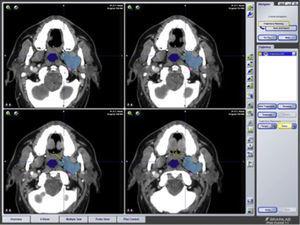

Control de márgenes

En cirugía oncológica de cabeza y cuello uno de los factores pronósticos más importantes es la resección completa del tumor y un buen control de márgenes. La planificación preoperatoria permite al cirujano simular las condiciones quirúrgicas con una excelente precisión (error menor de 1mm), permitiendo definir los márgenes de resección con más exactitud (figs. 3A y B). No se ha encontrado ningún trabajo que compare los resultados de la resección de tumores con las técnicas convencionales y las guiadas con navegación. Solo en un artículo5 se realiza un control intraoperatorio guiado con navegación de la resección de márgenes en 6 casos de cáncer avanzado de cabeza y cuello y se describen, sin análisis ni comparación posteriores, variables como la necesidad de resección adicional, márgenes histológicos, necesidad de RT postoperatoria, recurrencia y supervivencia. Los autores concluyen que puede ser una herramienta útil para mejorar el control local del tumor, porque permite visualizar si los márgenes de resección han sido adecuados tras la ablación tumoral y, por tanto, la necesidad o no de ampliar márgenes en el mismo acto quirúrgico.

A y B. Carcinoma epidermoide recidivante de piel. Navegación de los márgenes de resección.

Figura 3.

(0,31MB).